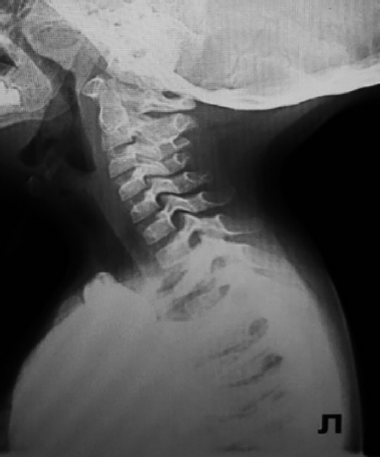

Ребенку была выполнена супраглоттопластика в объеме диссекции черпалонадгортанных складок и иссечения клиновидных хрящей (учитывая наличие клинико-эндоскопических признаков ларингомаляции 2-го типа) (рис. 3, а–с).

Рис. 3. Этапы супраглоттопластики (а–с). Клинок ларингоскопа установлен под корень языка